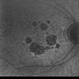

- geographic atrophy

- AMD, geographic atrophy